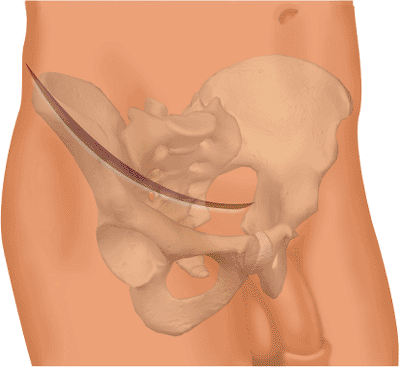

an approach to the anterior column of the acetabulum and the inner

aspect of the innominate bone. It allows exposure of the entire,

internal, iliac fossa and pelvic brim from the anterior aspect of the

sacroiliac joint to the pubic symphysis. The quadrilateral surface of

the innominate bone and the superior and inferior rami are also

accessible. Access to a portion of the external aspect of the ilium

also is possible (Fig. 42.1).

Figure 42.1. Access to the innominate bone with the ilioinguinal approach. (Redrawn with permission from

J. M. Matta, Surgical Approaches to Fractures of the Acetabulum and Pelvis. Copyright © J. M. Matta, 1996.

) |